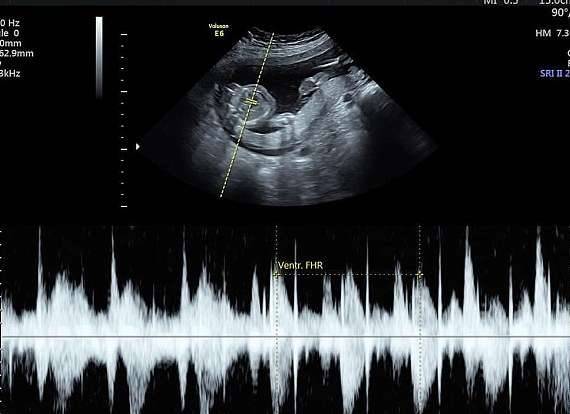

▼医生检查后发现,Keri腹中的宝宝身体健康,各项指标都很正常,但大脑畸形,没有存活的希望,建议她直接堕胎。

▼其实做出这个决定,对Keri来说并不容易。在接下来的怀孕过程中,她会感觉到胎儿的活动,女儿的小脚会踢打她的肚子,女儿的心跳会让她痛心。